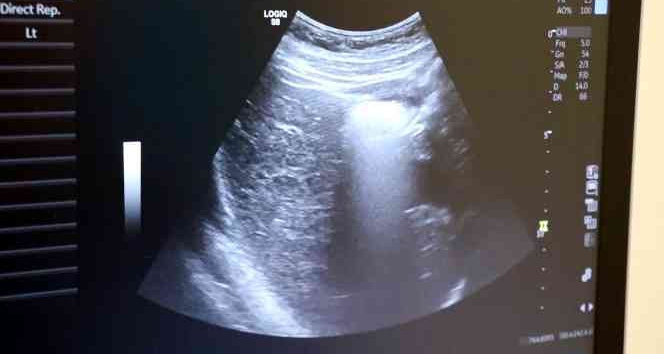

Ayrıntılı ve 4 boyutlu ultrason ile bebeklerin doğmadan önceki sağlık durumlarının belirlenebileceğine değinen Uzm. Dr. İlker Eroğlu, “Ultrason; yüksek frekanslı ses dalgalarının bilgisayar işlemcisinde işlenip, kablo arayıcılığıyla monitöre aktarılmasıdır. Son yıllarda gebelikte ayrıntılı ultrason gerekliliği giderek artmaktadır. Yaklaşık 50 yıl önce ultrason yaygın değilken doğumlarda bebek nasıl doğacak, sağlıklı mı sağlıksız mı doğacak ya da cinsiyet bile bilinemiyordu. 4 boyutlu ultrasonda ya da ayrıntılı ultrasondan sonra bebeğin sakatlıkları doğumdan önce anlaşılıp, tedavisi mümkün olanlar da doğumdan önce tedavi edilebilir oldu. Böylelikle bebeklerin daha sağlıklı olarak dünyaya gelmesi sağlanmış oldu. O nedenle ayrıntılı ultrason gereklidir” dedi.

Renkli ultrasonlarda bebeklerin anne karnındayken sakatlığı olup olmadığının belirlendiğini ifade eden İlker Eroğlu, “4 boyutlu ultrason halk arasında ‘renkli ultrason’ diye bilinir. Anneler bu ultrasonda bebeğin görüntüsünü anladığı için onu daha çok sever. Hekimler genelde ultrasona siyah-beyaz bakar. 4 boyutlu ultrason iç organlar hakkında detaylı bilgi vermez. Biz detaylı ultrasonda (2. düzey ultrason) bebeğin iç organlarına yönelik incelemeyi siyah beyaz olarak yaparız. O nedenle bizim için siyah-beyaz ve 2 boyutlu olarak yapılan inceleme daha önemlidir. 4 boyutlu ultrasonda da faydalandığımız yerler vardır. 4 boyutlu ultrasonda örneğin; bebeğin kolu-bacağı yoksa, dudak yarığı varsa, gösterebiliriz. Çeşitli anatomik deformasyonları da anneye gösterebiliriz. Hala dünyada ayrıntılı ultrason 2 boyutlu ve siyah-beyaz olarak yapılır” diye konuştu.